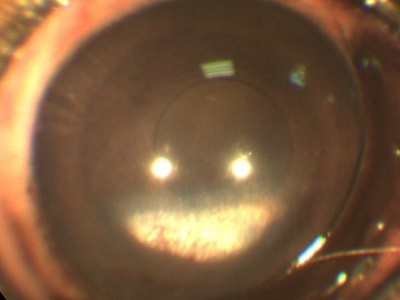

acumulare de săruri în suprafață și straturile profunde ale corneei, de asemenea, o vopsea albă.

Aceste modificări apar ca urmare a inflamatiei cronice, genetica, tulburări ale metabolismului, tulburări endocrine. Pentru fiecare cauză are propriile sale de cercetare și algoritmul acțiunilor.

De exemplu, atunci când bariera este lovit stratul lichid intern al corneei - endoteliului. Unele rase de câini au o predispoziție genetică la o scădere a numărului de celule endoteliale, care este motivul pentru care se umfla corneei si devine alb. De asemenea, în cazul în care numărul acestor celule este prin natura prea puține animale, dar cu varsta ele devin chiar mai mici.

În acest context, se poate dezvolta edem excesiv de puternic, separarea corneei, formarea de bule specifice (Bull).